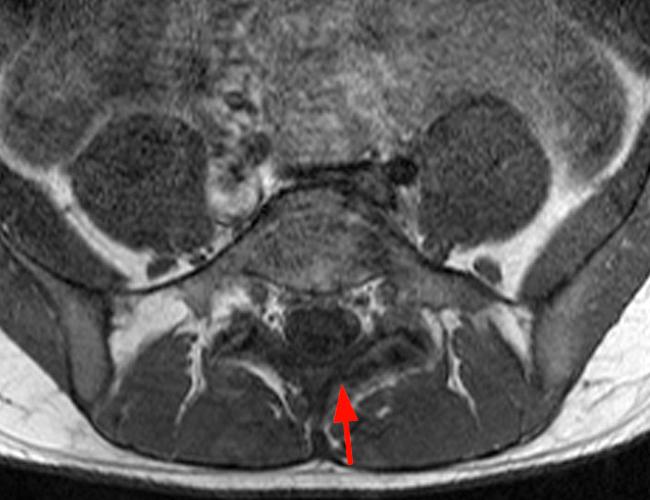

Case 2: T1-weighted (4A) and T2-weighted (4B) axial images show T1 hypointensity and T2 hyperintensity (arrowheads) in the left lamina of L5 adjacent to a small hypointense line (arrows) which traverses the lamina.

Case 2: Acute left-sided laminolysis